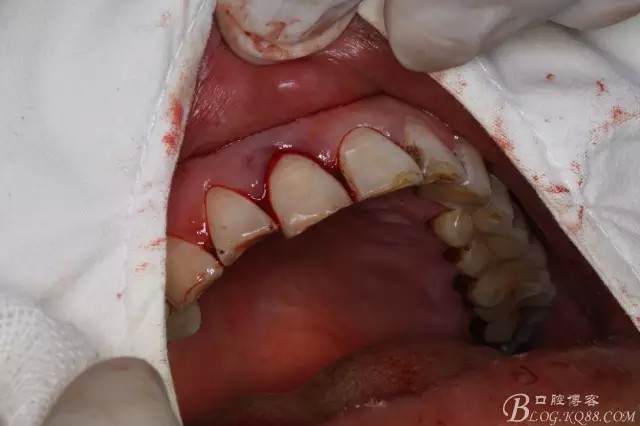

圖3.腭側(cè)牙周袋深約8mm.

圖4.唇、腭側(cè)局部浸潤(rùn)麻醉